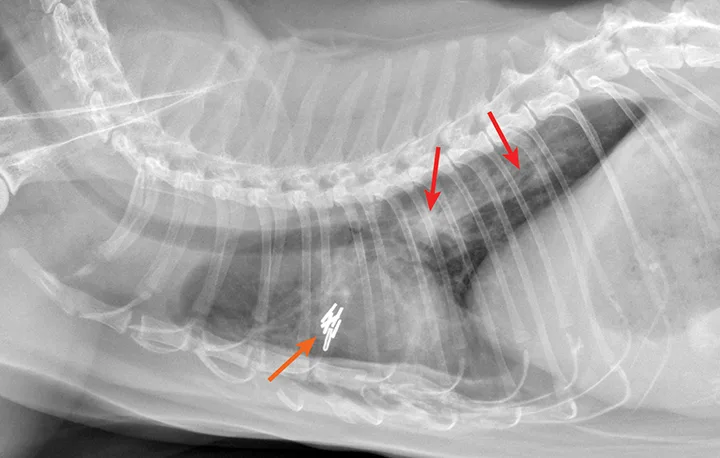

Radiographic evaluation is variable. Classic cranioventral distribution is less common in cats (Figure 3). A bronchial pattern is most common; however, bronchointerstitial, alveolar, and more structured pseudonodular patterns can occur.6,8 Occasionally, pulmonary abscesses may be appreciated and resemble pulmonary neoplasia (Figure 4).

FIGURE 3

Radiograph of bronchopneumonia with more classic cranioventral distribution (arrows). Other diseases, including CHF, have a similar distribution. Lack of this pattern does not rule out infection.